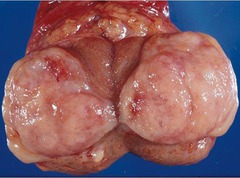

Leiomyoma

benign smooth muscle tumor